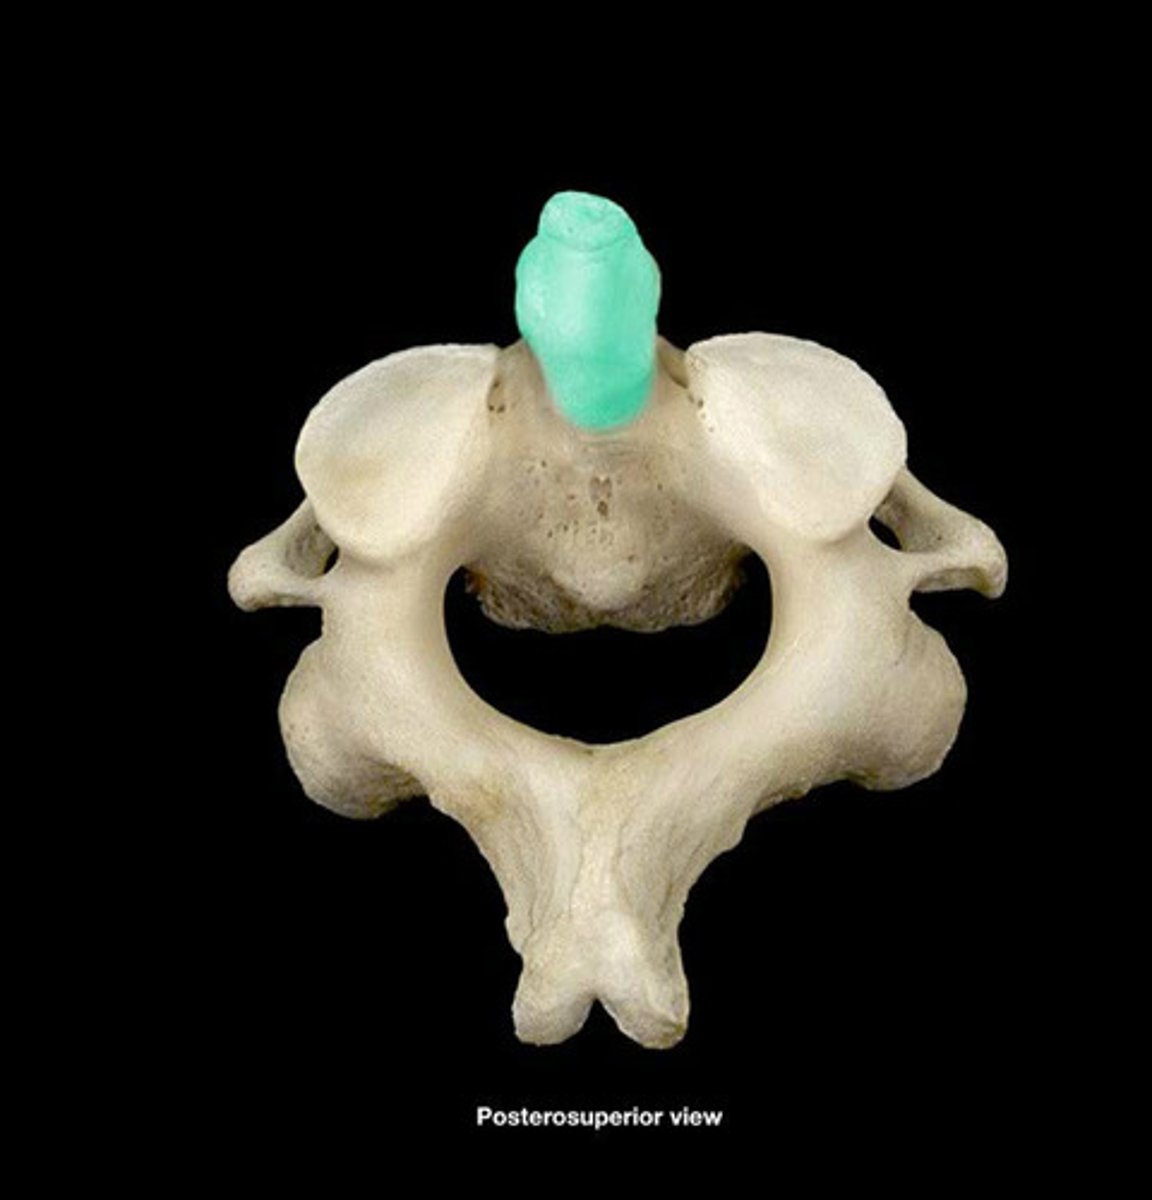

Atlas

Transverse Foramen

Axis (C2)

Odontoid Process